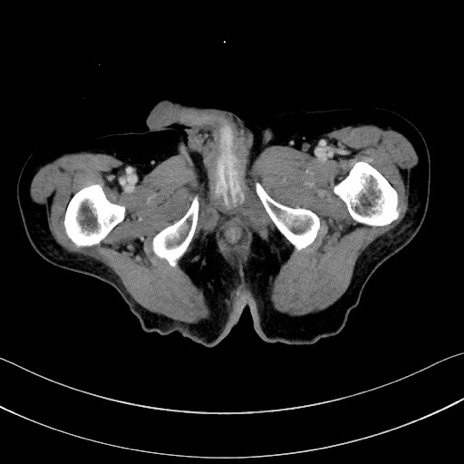

症例28(横断像)

【症例】60歳代男性

【主訴】嘔吐

【現病歴】胃癌にて胃全摘後。食思不振が悪化し、夜中に嘔吐することがある。

【既往歴】胃癌、胃全摘、脾摘、胆摘後

【データ】WBC 5900、CRP 10.56